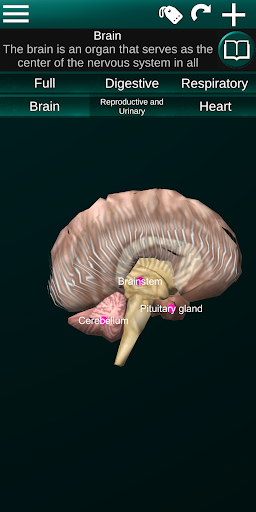

* Otak, yang meliputi otak, otak kecil, dan batang otak.